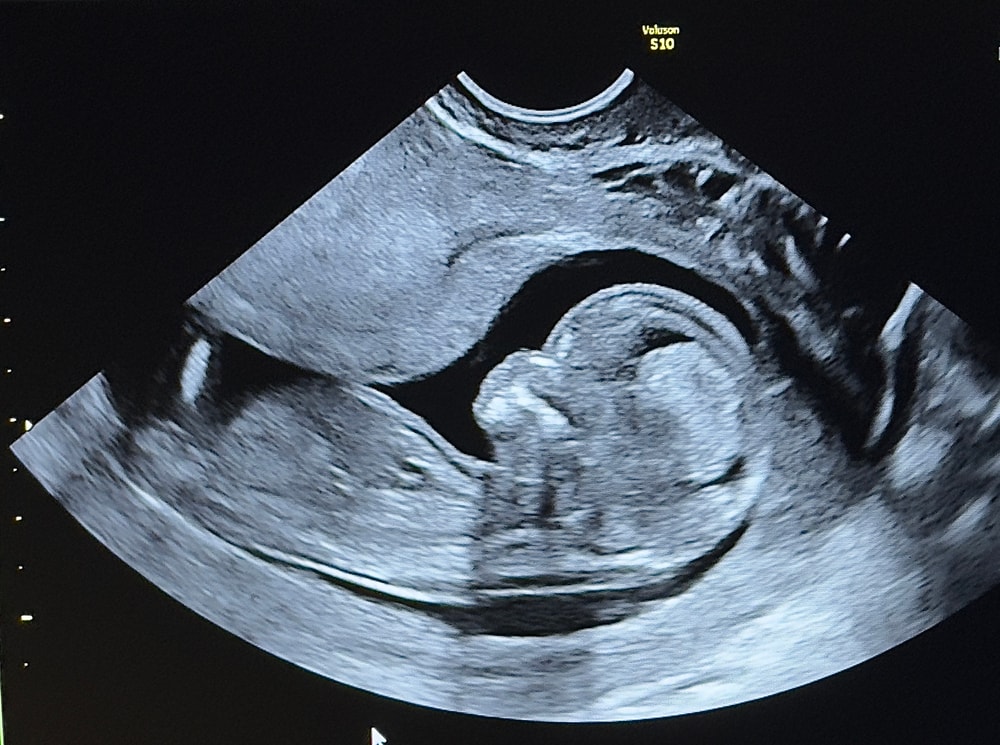

Сегодня была на узи , вроде бы врач сказала однозначно мальчик , но сомнения послу двух дочек не оставляет в покое 🥲

может ли быть что это пуповина ?